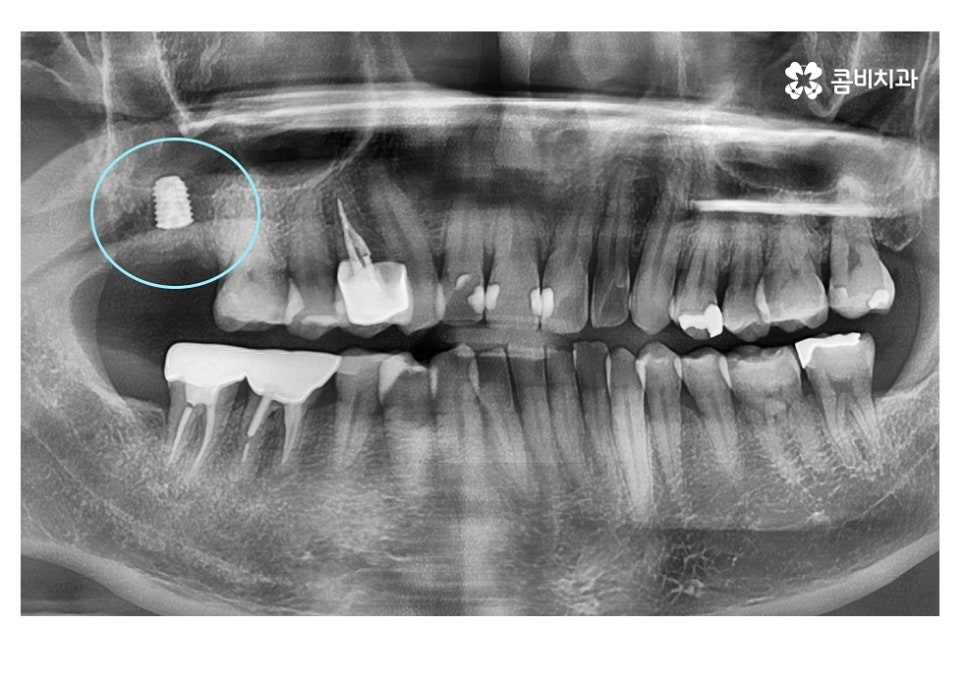

보통 임플란트와 교정을 같이 해야 하는 케이스에는

교정이 끝나기 약 6개월 전에 치료를 하게 되는 경우가 많은데

임플란트 식립 후 뼈가 완전히 굳고 치료를

마무리하기까지 보통 4~5개월 정도 걸리기 때문에

발치와 임플란트의 시술 그리고 교정이 비슷한 시기에

끝날 수 있도록 치료 계획을 세우고 있어요.